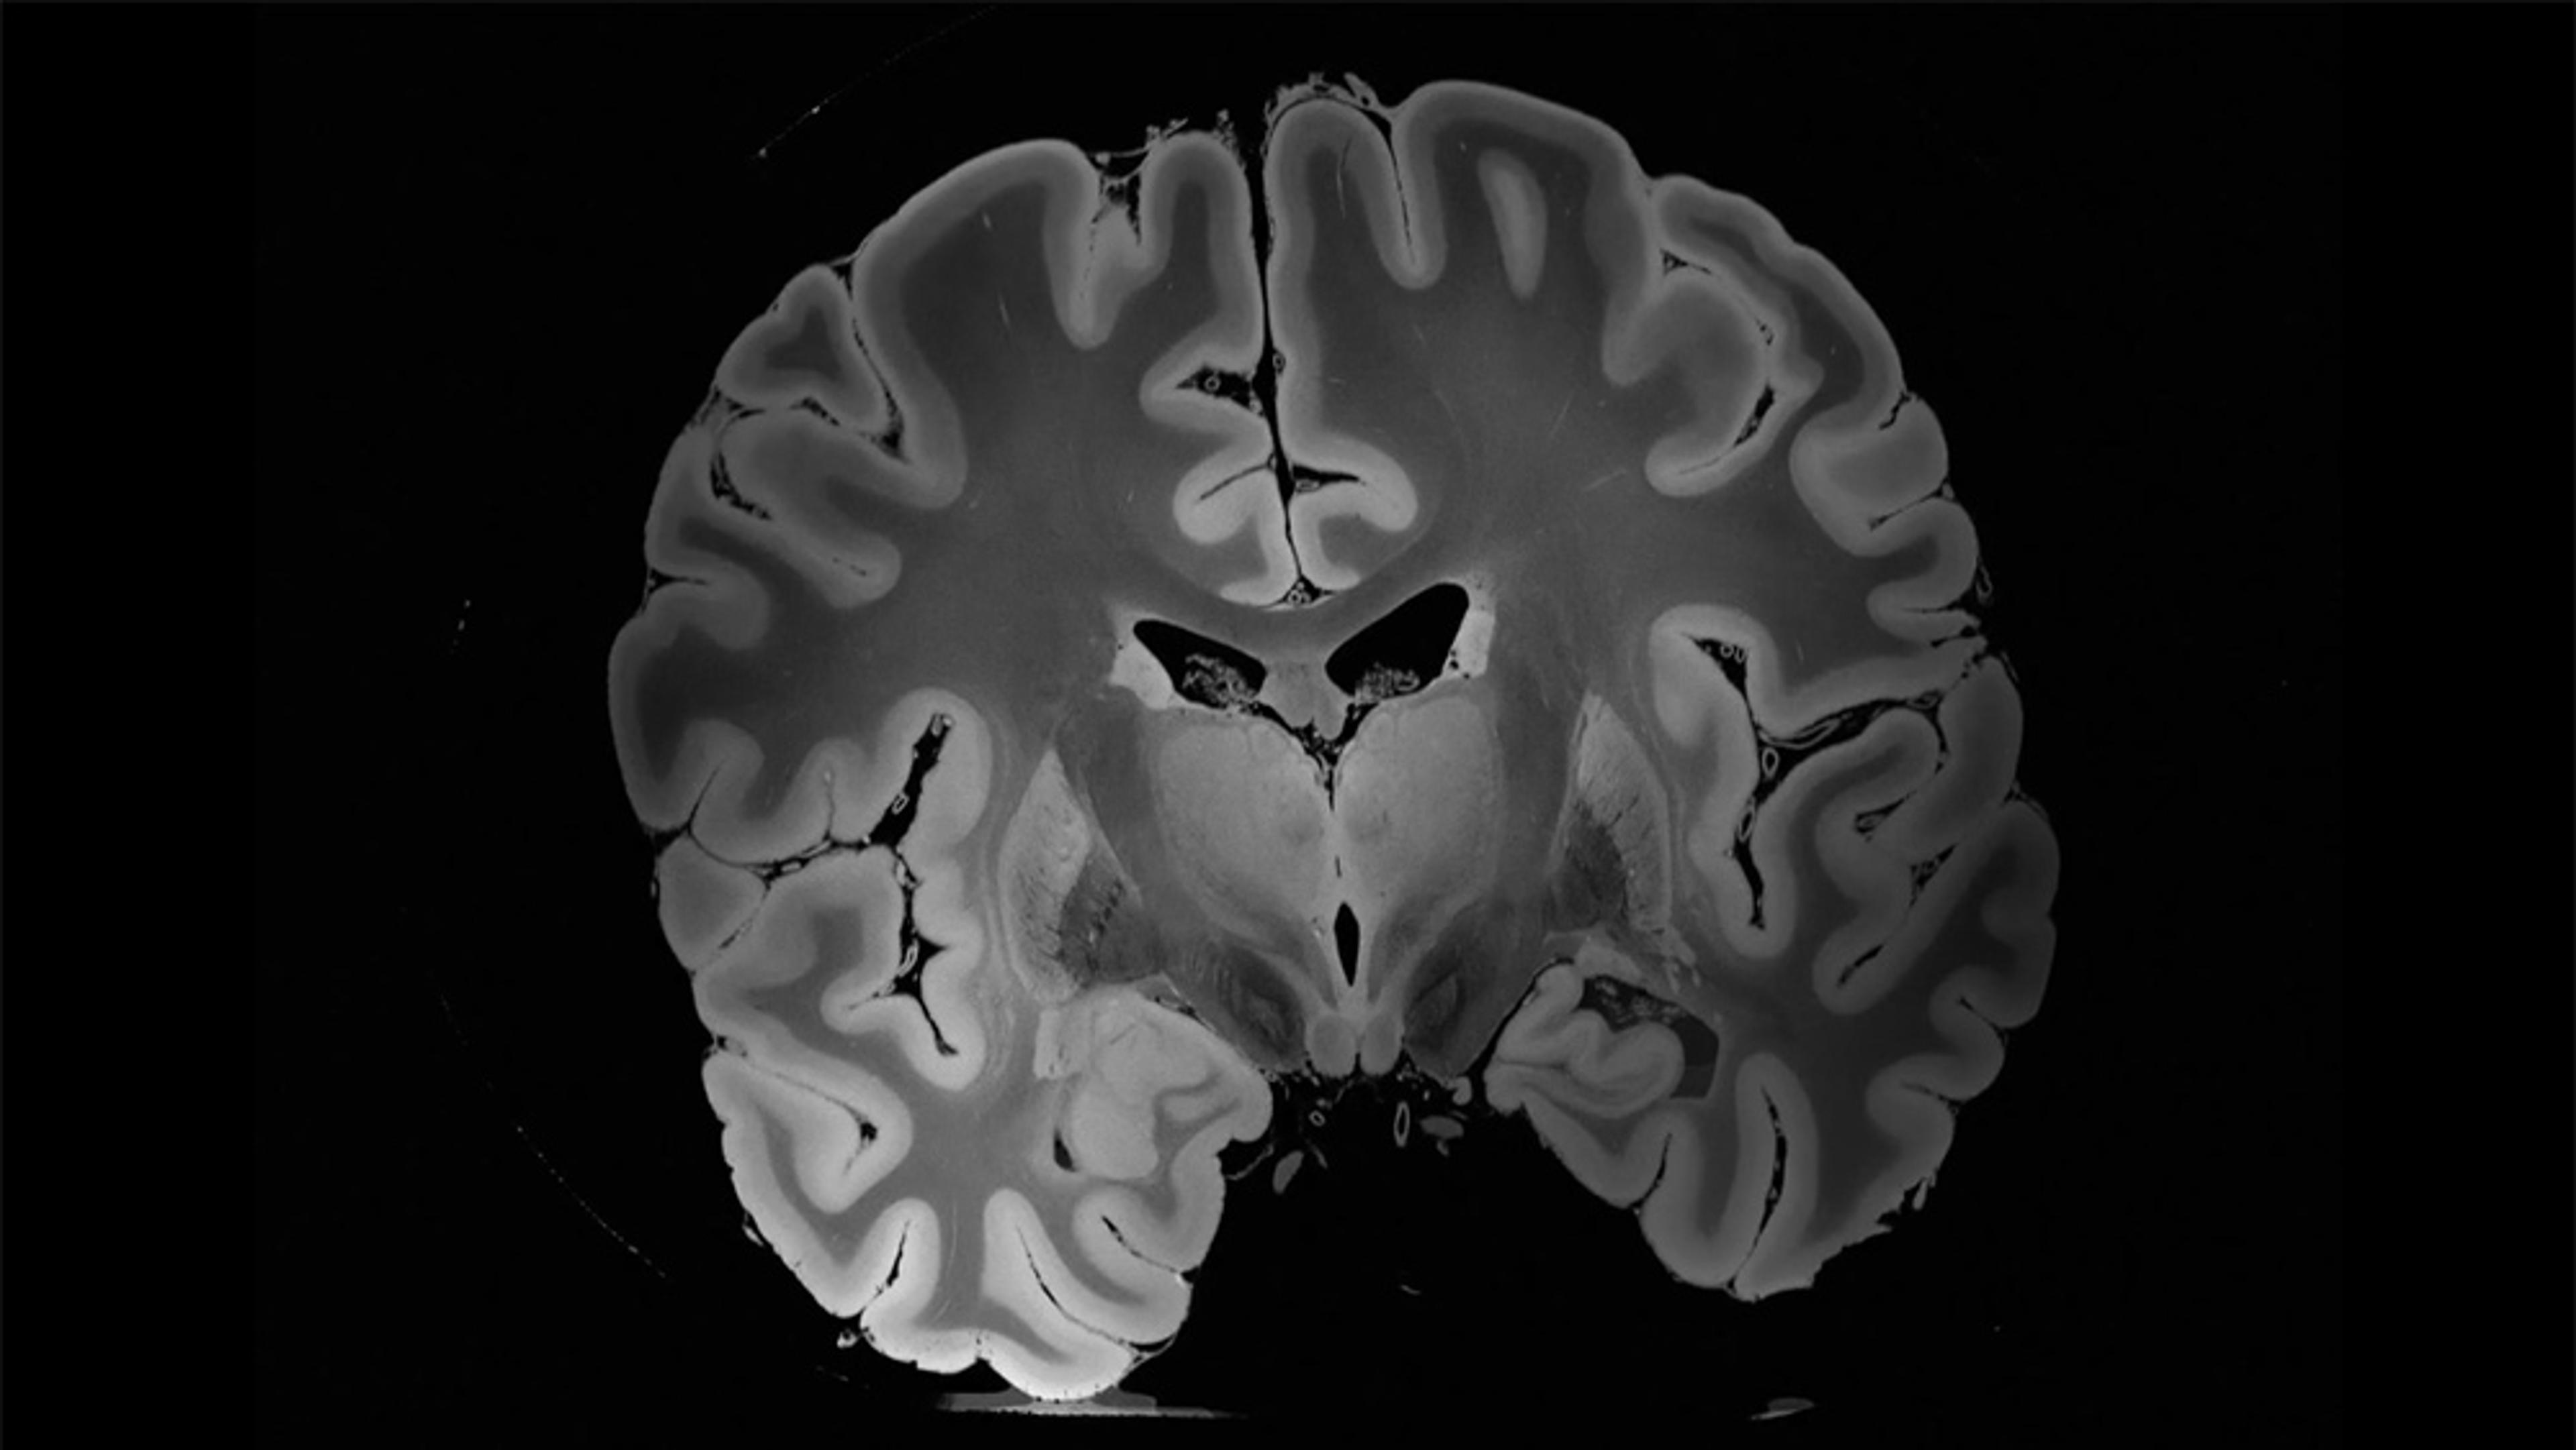

The UK research scientist Susan Greenfield believes that neuronal assemblies – coalitions of millions of brain cells that activate and disband over a scale of millimetres and milliseconds – could be a Rosetta Stone for explaining shifts and differences in states of consciousness. Although research about these cellular systems is still in its early stages, Greenfield thinks that further study could help neuroscientists bridge the chasm between the local neural networks and large brain regions that currently characterise our framework for perception. And, as she proposes in this interview with Robert Lawrence Kuhn for the PBS series Closer to Truth (2000-), bridging this gap might be key to unlocking some of the foremost puzzles of consciousness – from sleep, dreams and wakefulness to mental illness.

Why don’t we feel pain in dreams? The answer might lie in a new frontier of neuroscience